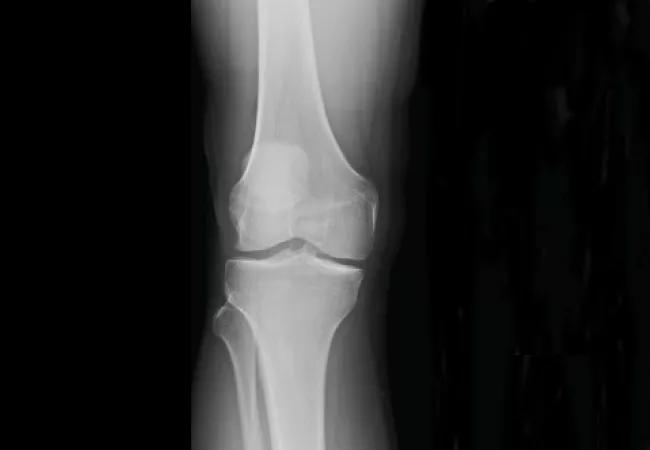

Our results showed that lateral compartment joint space width was slightly narrower in the ACL reconstructed knees compared to the contralateral control knees, which represents the earliest sign of post-traumatic osteoarthritis in this part of the joint (See radiographs).

Radiographs showing lateral compartment joint space width.

Patients with partial lateral meniscectomy showed about 0.4 mm of joint space narrowing compared to patients with no tear. We saw no significant difference among patients with meniscus repair, untreated stable tear and no tear. This suggests that lateral meniscus repair effectively preserves joint space width and prevents the worsening of post-traumatic osteoarthritis in the lateral compartment after ACL reconstruction. In contrast, our previous study demonstrated that both meniscectomy and repair were associated with narrower joint space in the medial compartment.